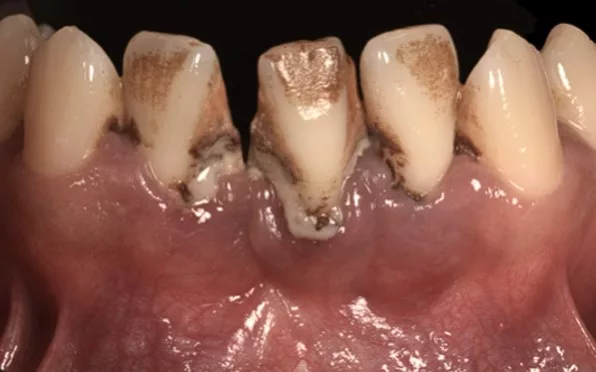

Préalable à tout traitement parodontal, la thérapeutique initiale, non chirurgicale, cherche à décontaminer les surfaces des racines dentaires, et notamment les zones situées sous la gencive. En effet les bactéries adhèrent très fortement à ces régions. Leur persistance, si elles ne sont pas rapidement éliminées, produit un effet pathogène (inflammation, abcès) pour les tissus de support des dents (gencive et tissu osseux).

Des bains de bouche (antiseptiques) ou des antibiotiques ne suffisent pas à les éliminer. Aussi des techniques manuelles ou ultrasoniques, indolores, sont indispensables décontaminer les surfaces colonisées par la plaque et le tartre.